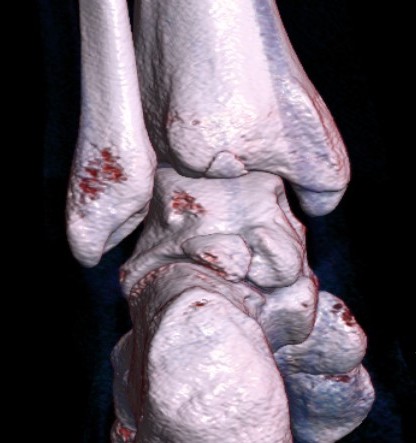

CT

Os trigonum

Fractured Stieda process

Os trigonum with osteochondral fracture posterior tibia